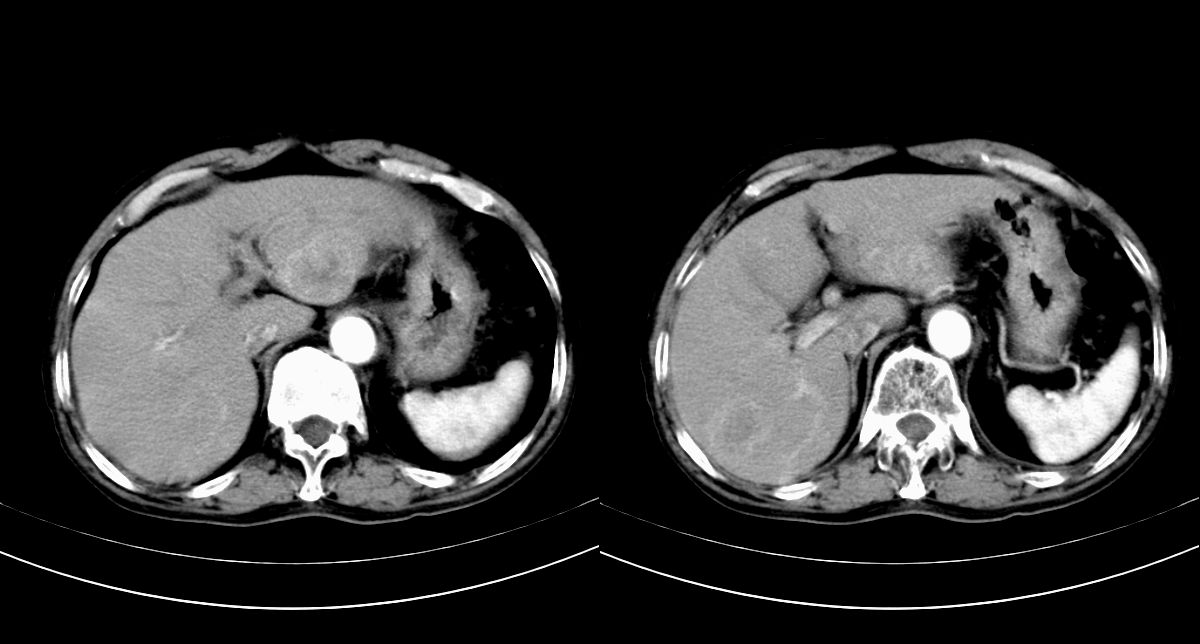

男,79y,无不适。体检发现肝脏占位。

肝内多发低密度结节,增强动脉期明显强化,门脉期逐渐下降,内有液化坏死区。

诊断:

肝细胞癌(结节型)

鉴别:肝转移癌。

肝内多发低密度结节灶,增强动脉期明显不规则环状强化,;门脉期逐渐下降,肿瘤壁厚薄不一,内有坏死液化区。

诊断:肝转移癌可能

鉴别:1原发性肝癌(强化方式符合,建议查afp)

2肝脓肿(无临床病史支持)